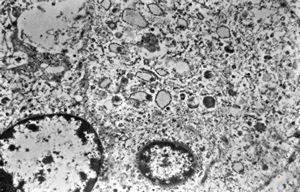

M, 43y. | myeloid leukemia

M, 43y. | myeloid leukemia … Auer bodies